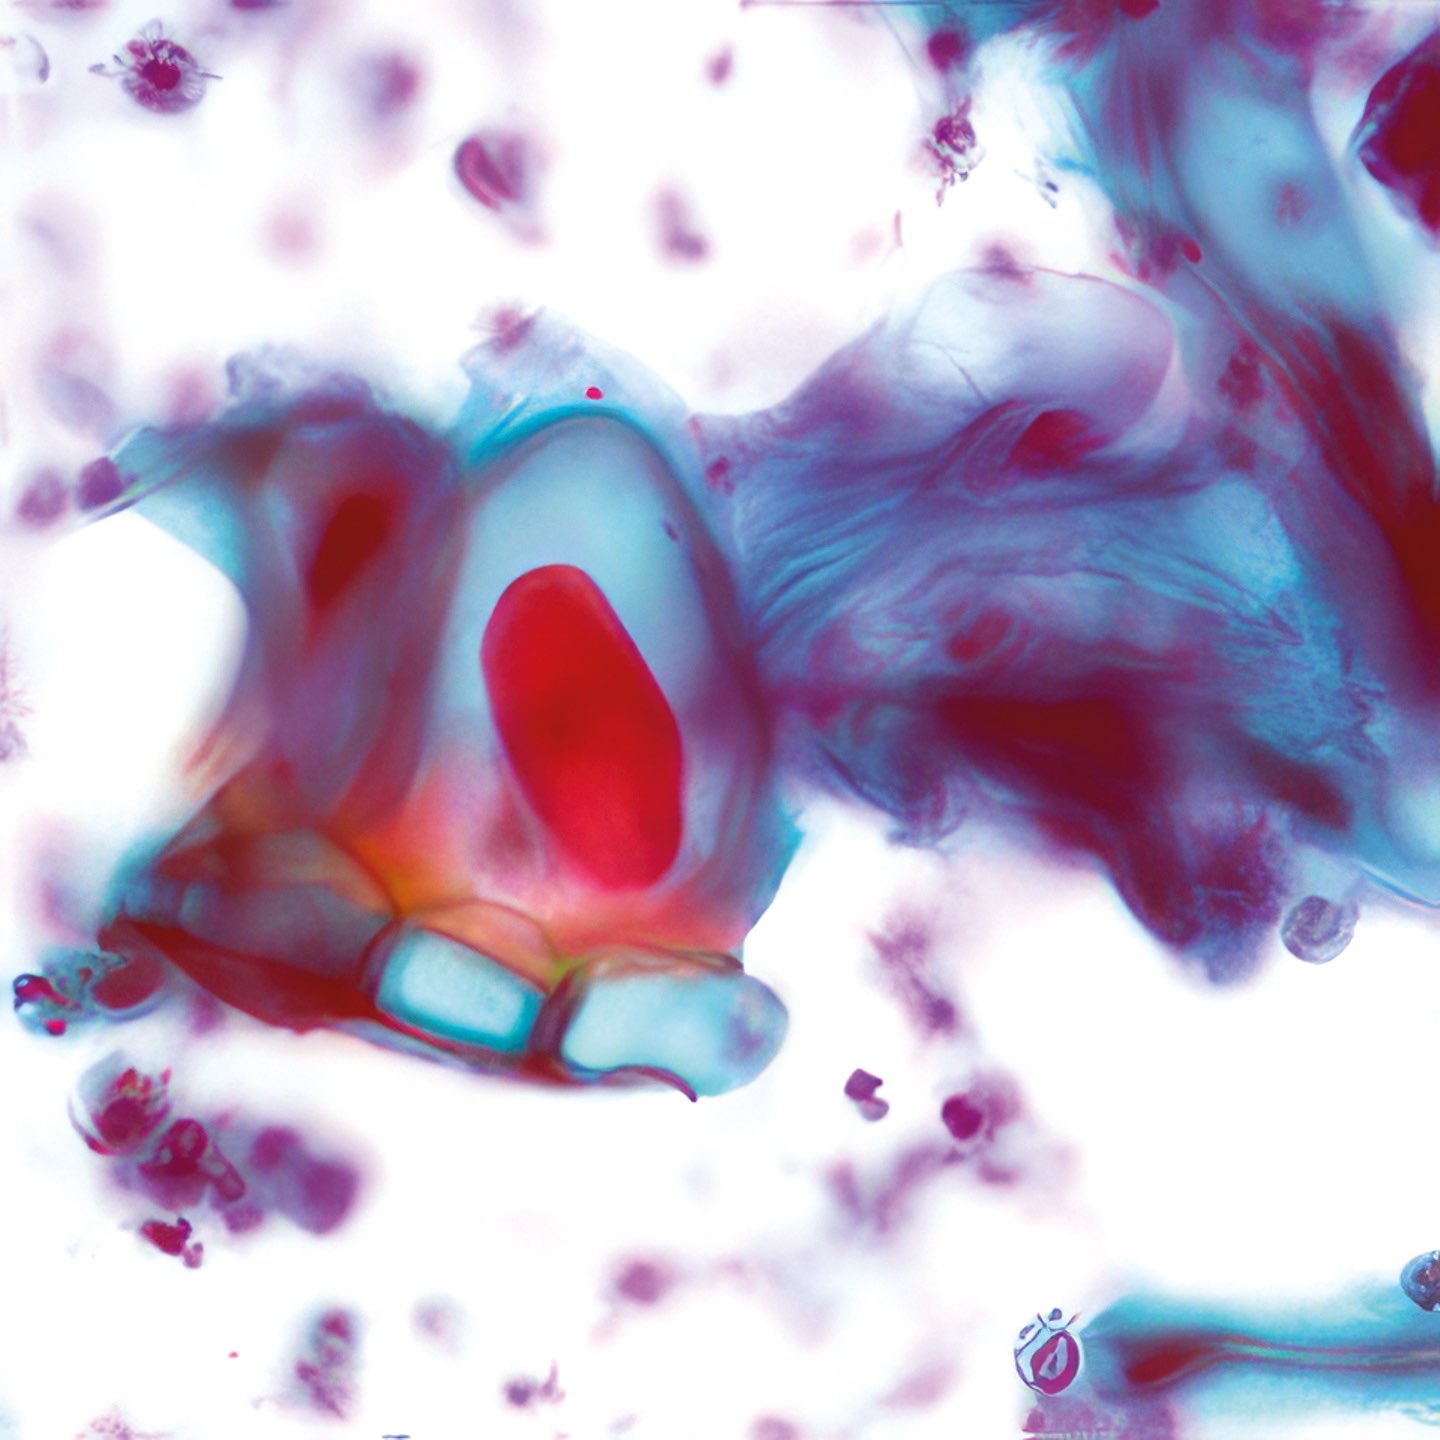

(Abbildungen 3 - 6: Pap, Vergrößerung 1000x)

Makroskopisch zeigt die areoläre Haut (Brustwarzenhof) eine feine ekzemartige nässende granuläre Struktur; die Brustwarze ist nicht eingezogen (Abb. 1 und 2). Die extrem atypischen Zellen liegen verstreut (Abb. 3), oder bilden lose zusammenhängende Gruppen (Abb. 4, 6). Einige sind doppelkernig. Im Vergleich zum gewöhnlichen Mammakarzinom sind sie extrem pleomorph und ihre Kerne sind stärker hyperchromatisch, sehr grob strukturiert, und zeigen manchmal prominente Chromozentren. Das Zytoplasma ist unterschiedlich breit und erscheint manchmal als vakuolär.

Histologie

Das durch Stanzbiopsie gewonnene histologische Präparat zeigt viele große, scheinbar vakuolisierte Zellen innerhalb des Plattenepithels. Eine PAS-Färbung war nicht möglich.